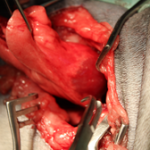

犬の肺腫瘍 手術法:右後葉肺葉切除術

当病院のレントゲン検査でも肺腫瘍が認められたため、咳の症状も腫瘍によるものと診断、飼い主様の希望により肺腫瘍摘出手術を行いました。

術後は良好に経過し、手術後6日目に退院されました。病理検査にて肺乳頭状腺癌との診断でした。現在は他の肺に転移しないように抗がん治療を受けていますが、元気いっぱいで過ごしています。いつまでも元気で長生きしてほしいですね(^0^)